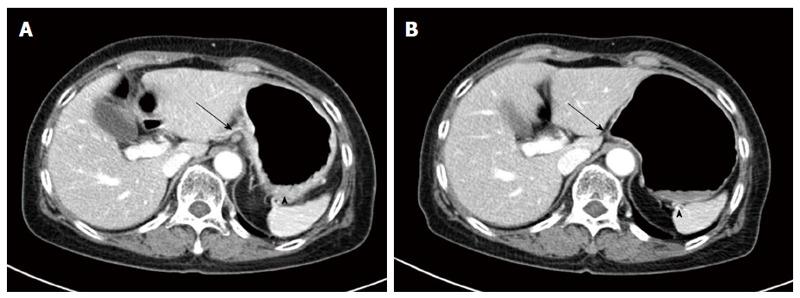

Breast cancer with stomach metastasis rare with an incidence of 1% or less among metastatic breast cancer patients. We experienced a case of breast cancer metastasizing to the stomach in 65-year-old female patient. She experienced dyspepsia and poor oral intake before visiting the clinic. Diffuse infiltration with nodular mucosal thickening of the stomach wall was observed, suggesting advanced gastric cancer based on gross endoscopic finding. Spread of poorly cohesive tumor cells in the gastric mucosa observed upon hematoxylin and eosin stain resembled signet ring cell carcinoma, but diffuse positive staining for GATA3 in immunohistochemical stain allowed for a conclusive diagnosis of breast cancer metastasizing to the stomach. Based on the final diagnosis, systemic chemotherapy was administered instead of primary surgical resection. After 2 cycles of docetaxel administration, she showed a partial response based on abdominal computed tomography scan. This case is an unusual presentation of breast cancer metastasizing to the gastrointestinal tract.

乳腺癌胃转移罕见,在转移性乳腺癌患者中的发生率为1%或更低。我们遇到一例65岁女性患者,乳腺癌转移至胃。她在就诊前出现消化不良和进食不佳。基于胃镜大体检查结果,观察到胃壁弥漫性浸润伴结节状黏膜增厚,提示进展期胃癌。苏木精-伊红染色显示胃黏膜中低黏附性肿瘤细胞扩散,类似印戒细胞癌,但免疫组化染色中GATA3弥漫性阳性染色可确诊为乳腺癌转移至胃。基于最终诊断,给予全身化疗而非一期手术切除。多西他赛给药2个周期后,根据腹部计算机断层扫描显示她有部分缓解。该病例是乳腺癌转移至胃肠道的不寻常表现。